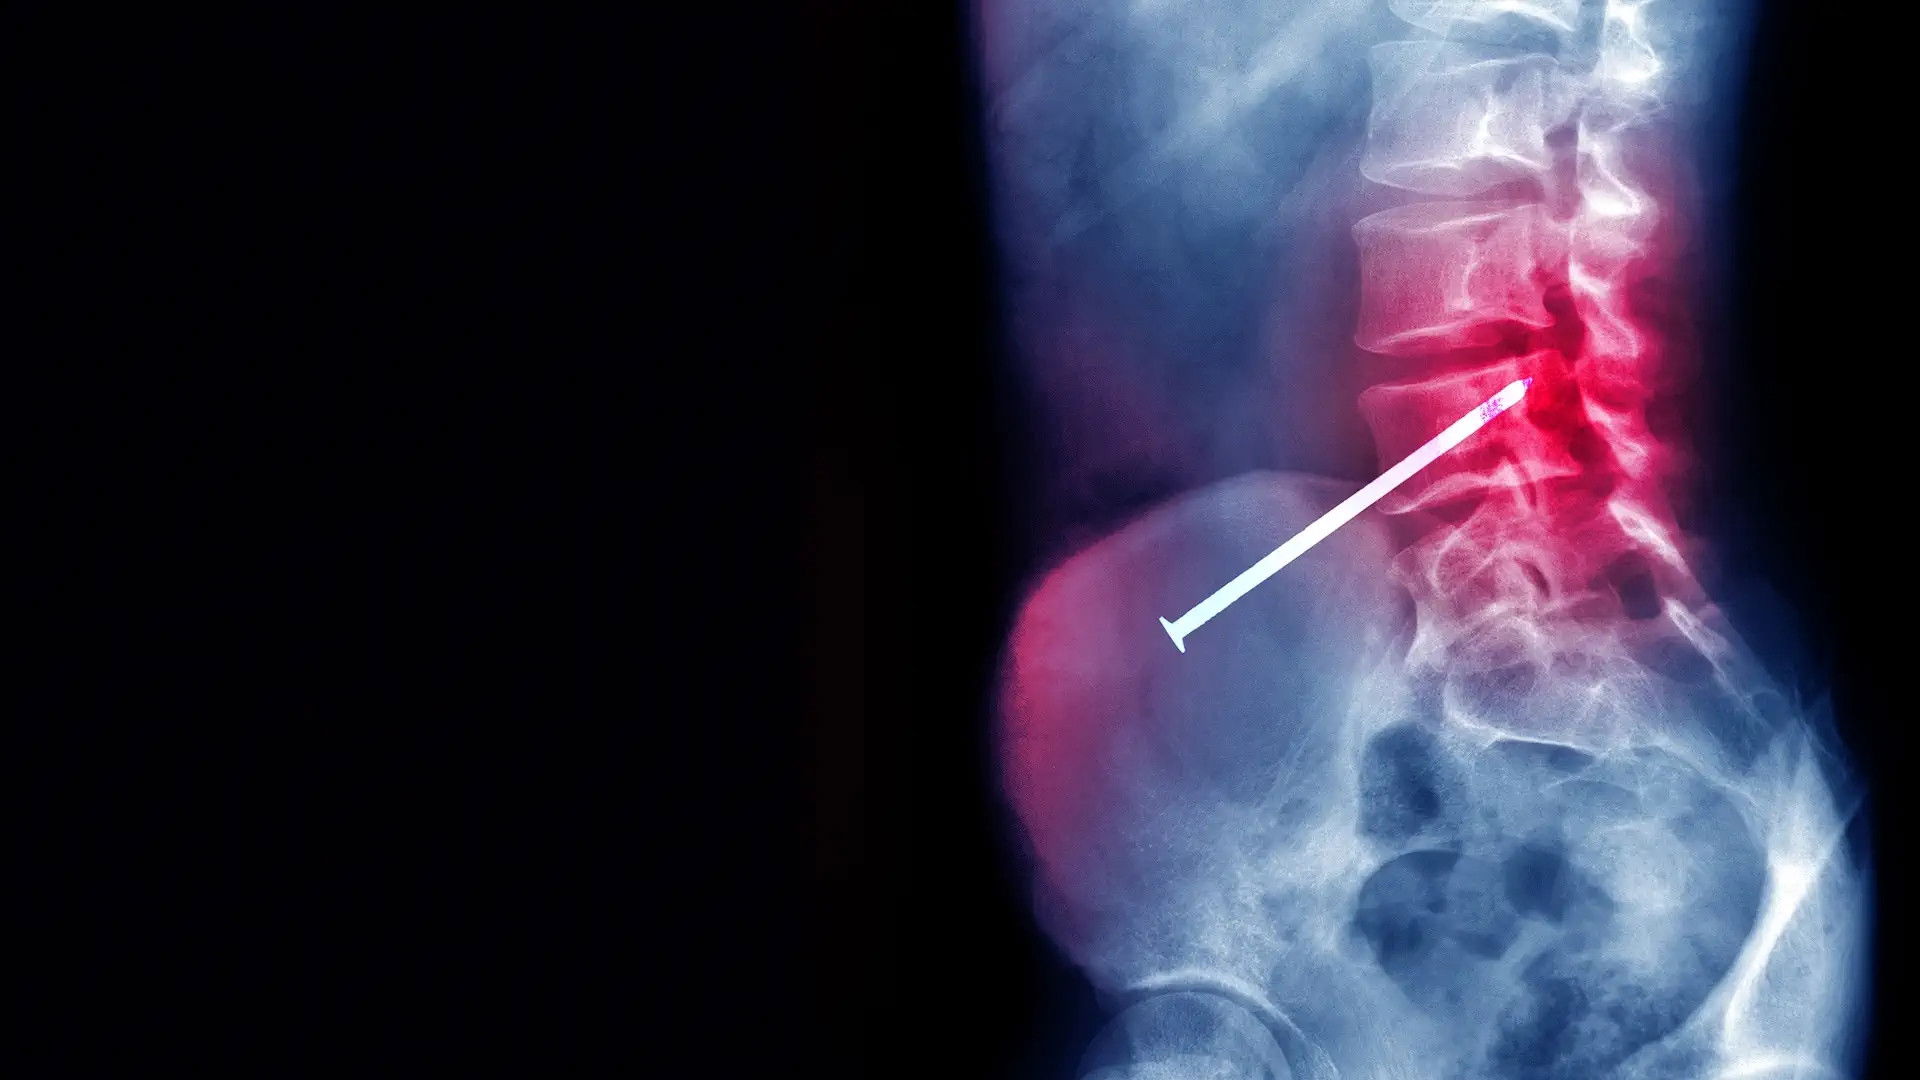

Documentary